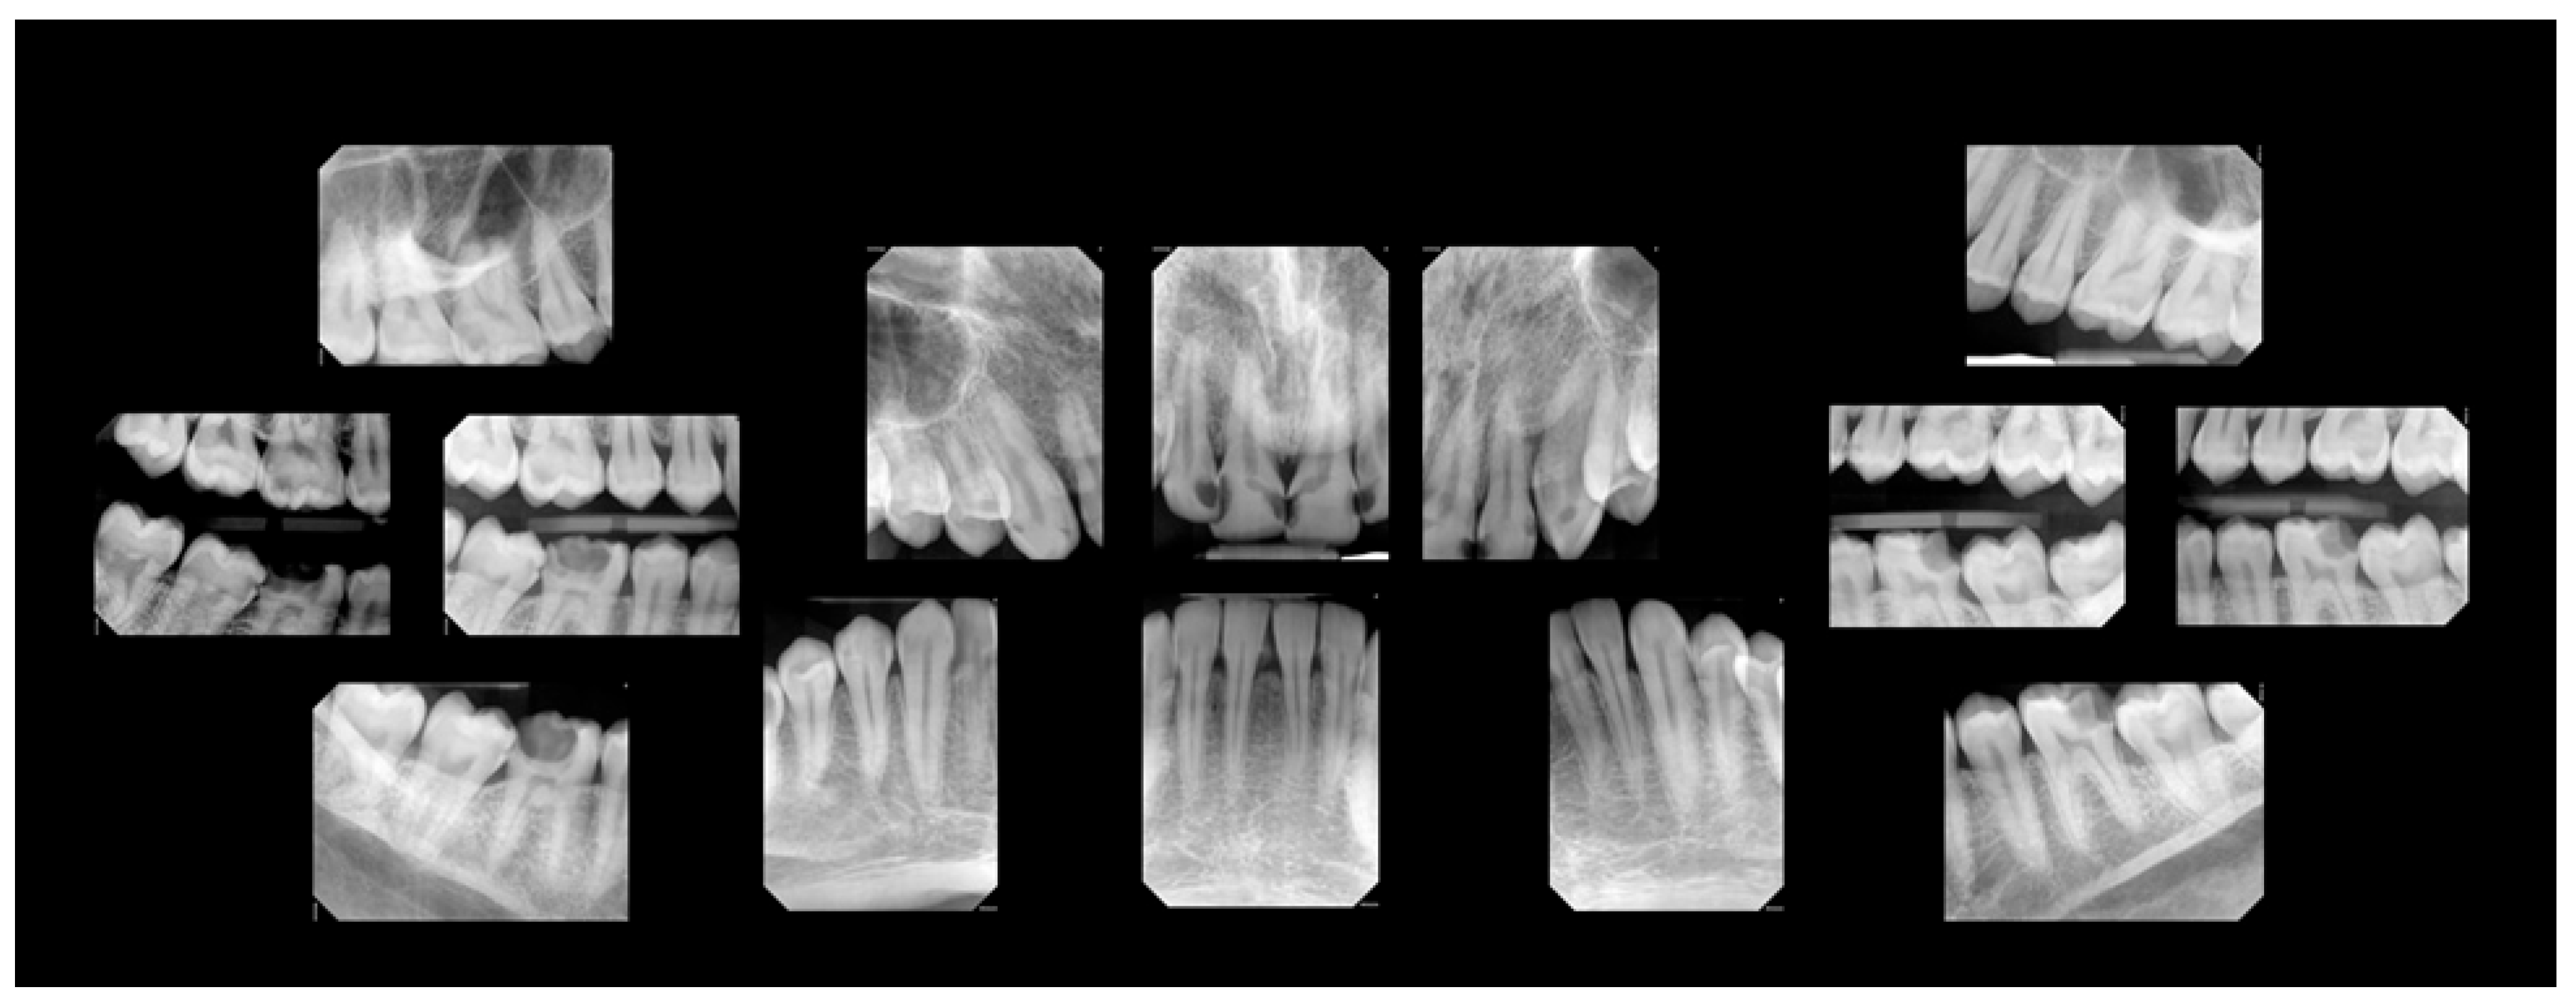

2. Case Presentation

2.1.1. Baseline Exam

2.1.2. Dental Treatment